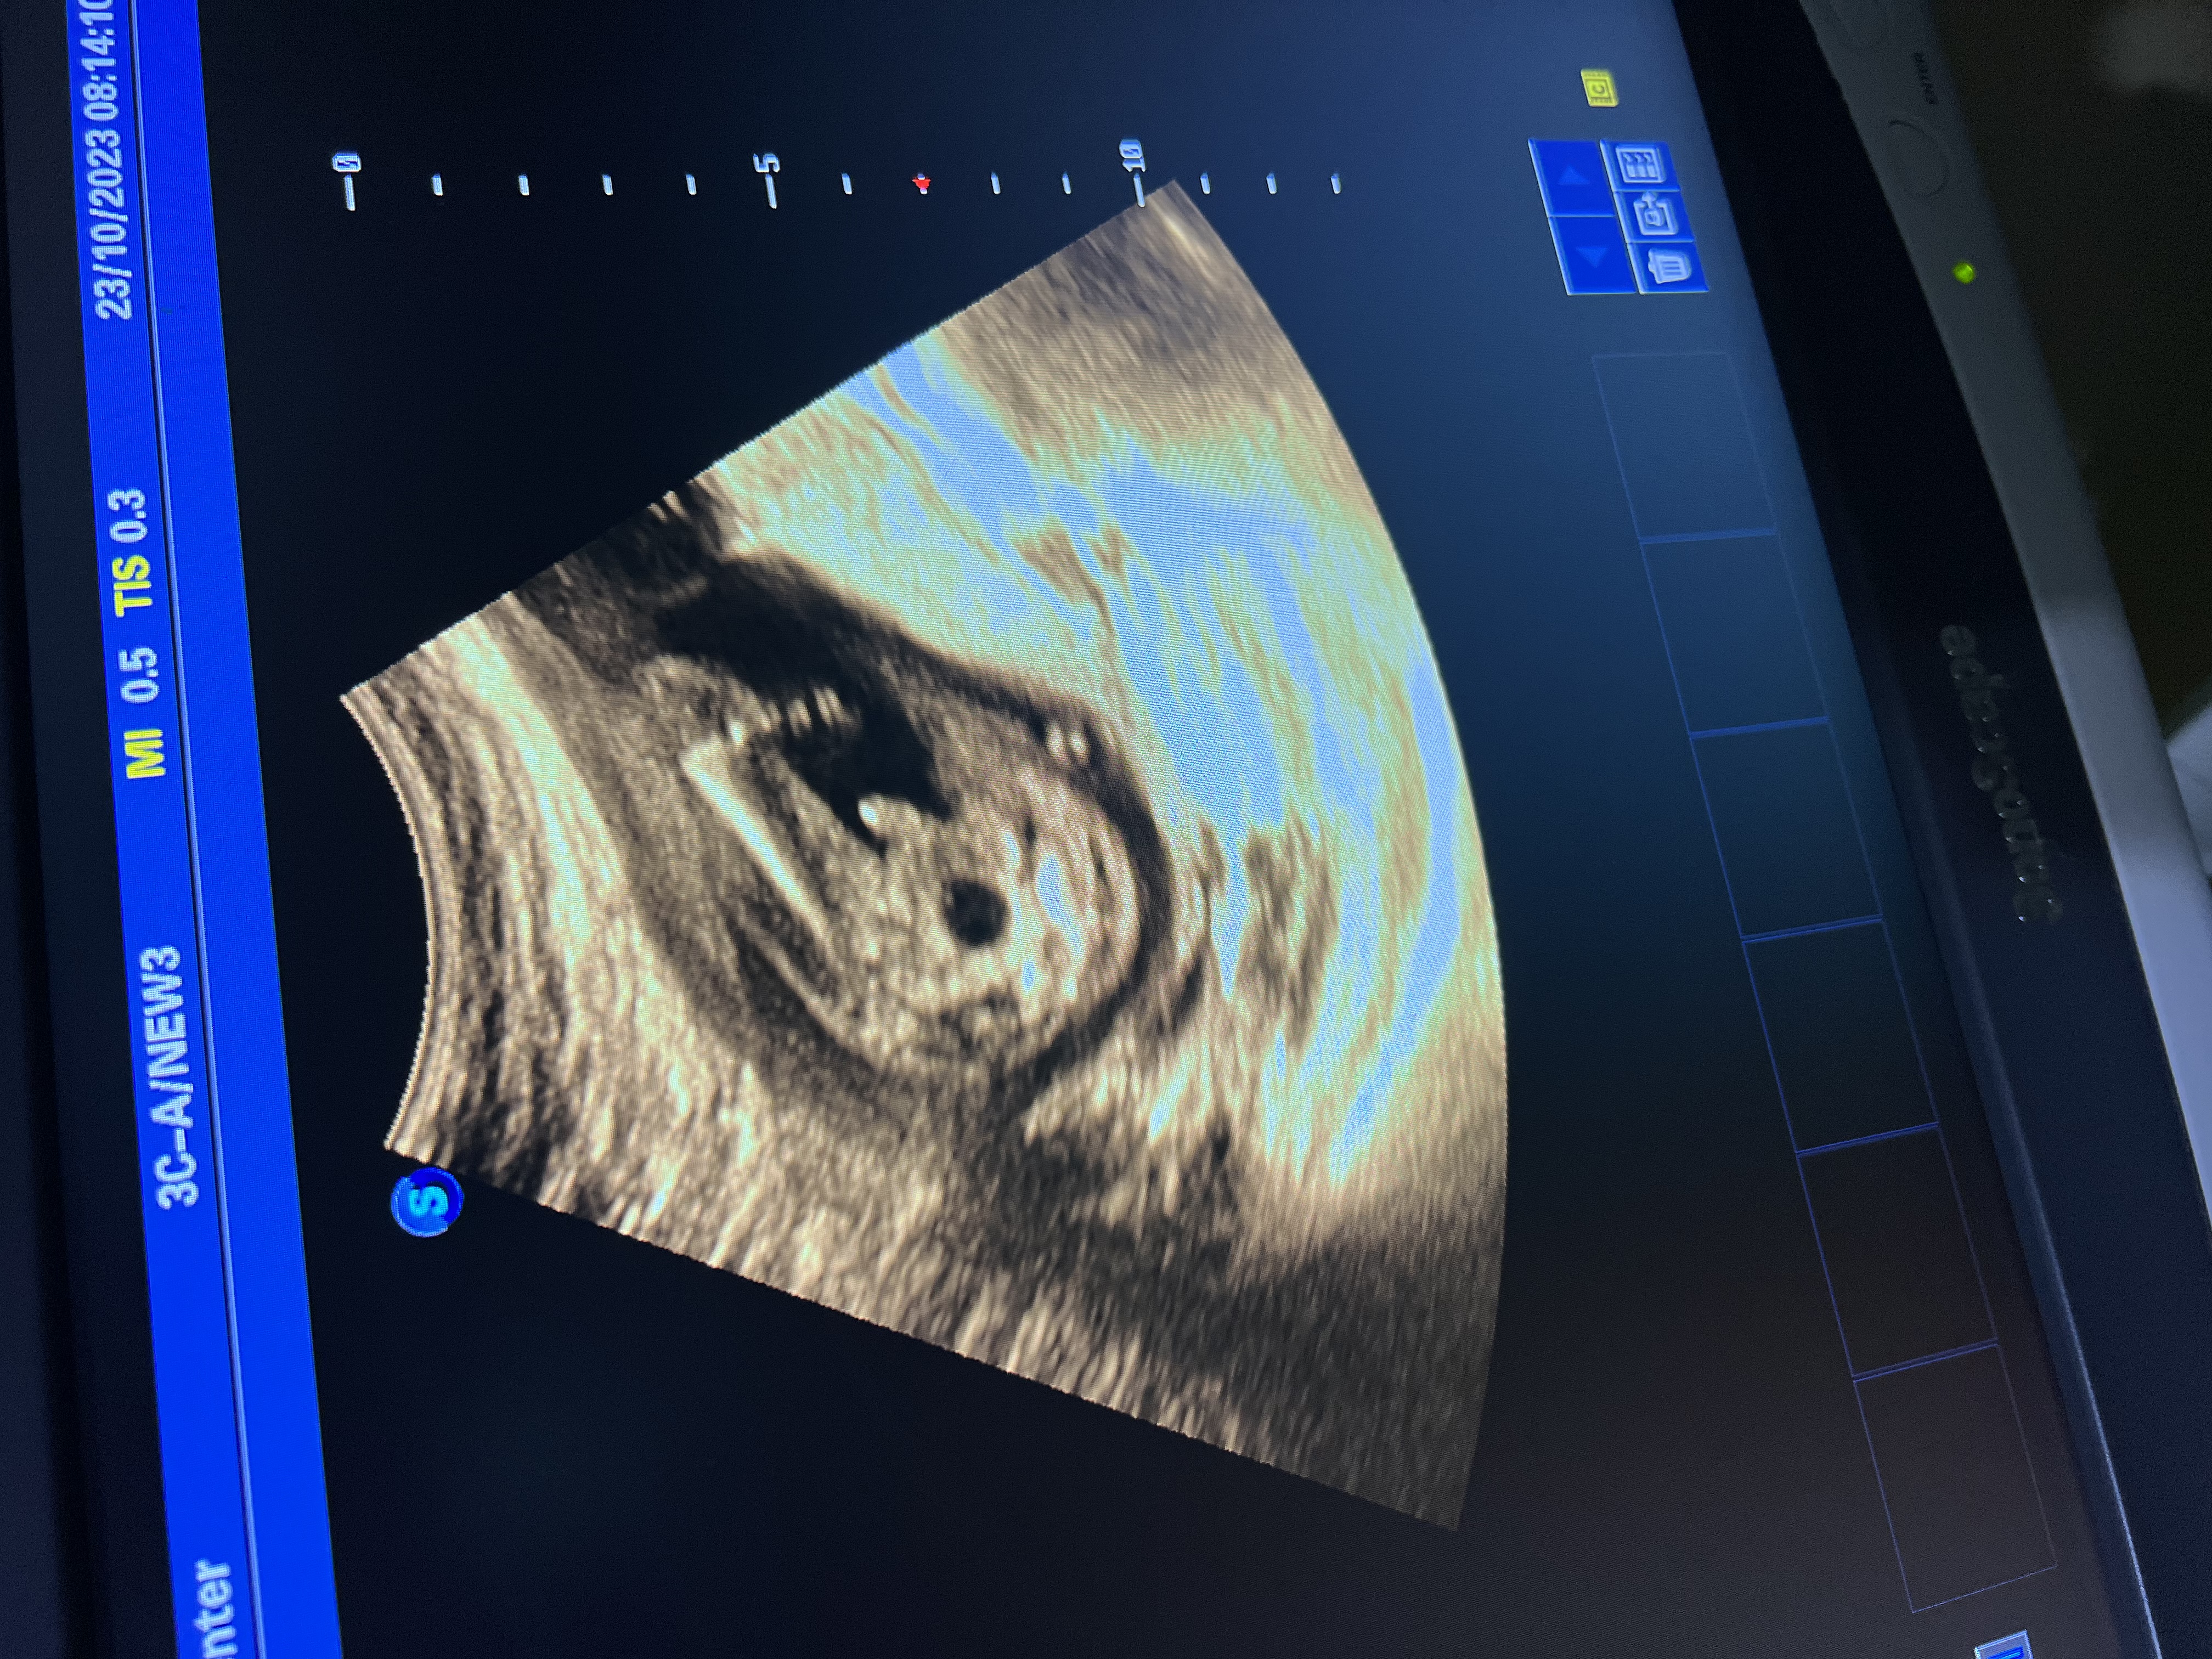

مقعده جنين الشهر الخامس ذكر ام انثى؟

هل جنين ذكر ام هذا الحبل السري

انا الحمل في شهر الثامن ولا اعرف نوع جنين احسب ما عندي جنين ذكر ام انثى